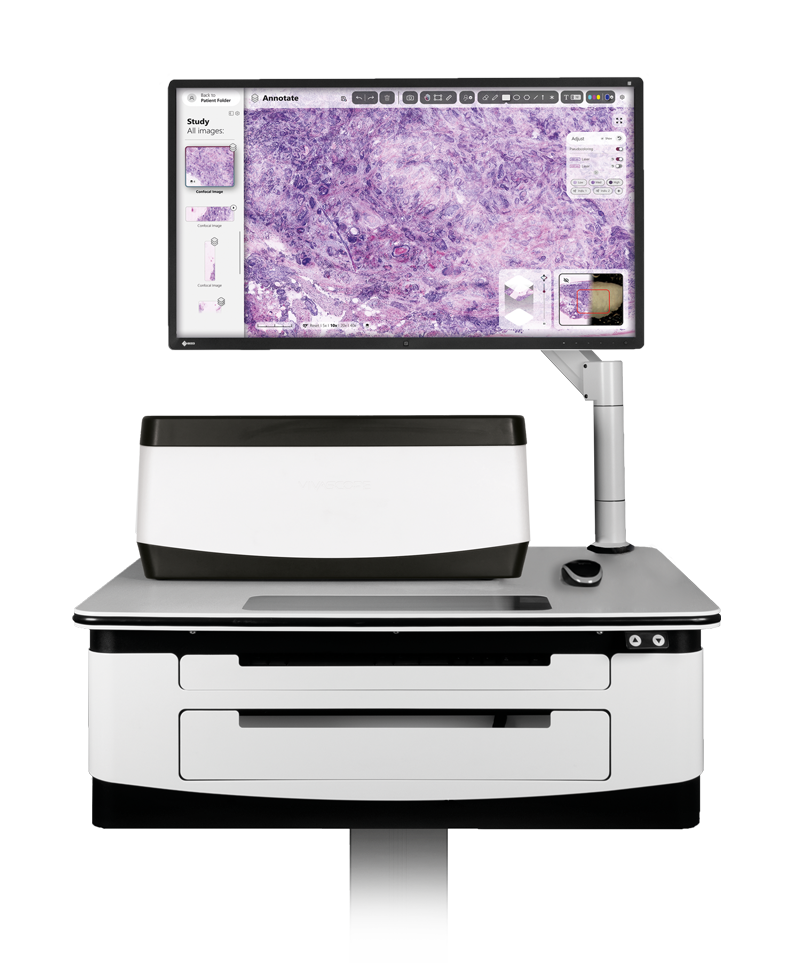

The VivaScope 2500 Ex Vivo technology offers H&E-like images, generated from two components. Two lasers of different wavelengths create two distinct images, a fluorescence image and a reflectance image. Both signals are scanned simultaneously and are used to create pseudo-colored images. The device’s software uses an algorithm to translate the acquired image information into colors that resemble H&E.

Access your sample morphology.. Within 5 minutes.

The VivaScope 2500 rapidly scans the excised tissue and reveals the cellular morphology right at the bedside. The examined tissue remains unharmed by the procedure and can be preserved for later histopathological analysis.

H&E-like digital images. At the bedside during surgery.

High resolution images of unfixed tissue without sectioning. Within 5 minutes, digital and on the bedside. The device’s software uses an algorithm to translate the acquired image information into colors that resemble H&E.

Evaluation of tumor margins

The VivaScope 2500 allows you to assess tumor margins intraoperatively. The Ex Vivo technology offers many advantages over frozen section analysis for microscopically controlled surgery. The time needed to complete a surgery can be reduced significantly. Integrated into a surgical workflow, VivaScope scans provide information comparable to H&E images derived from FFPE or frozen sections.